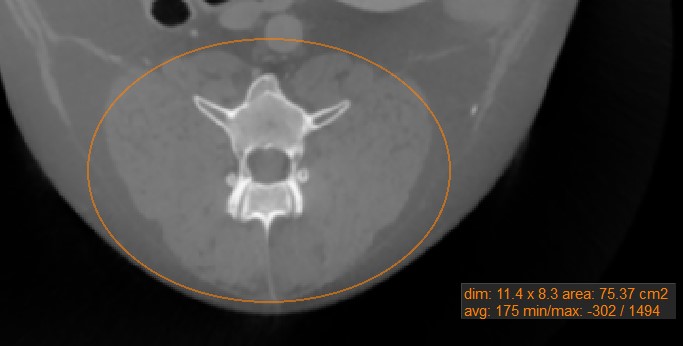

Oval

Mark oval areas of the active image slice by using the Oval measurement tool.

Select the Oval tool and assign it to one of the available mouse buttons. Start the measurement by pressing on the active image slice and drag the mouse to obtain an oval shape. Release the mouse when satisfied with the size of the marked area.

All available measurement values are displayed alongside the measurement.

Modify the marked area by moving one of the four points describing the rectangle around the oval shape using the Default tool.